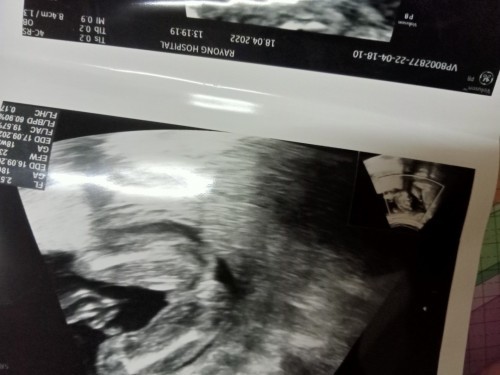

พุชายค่ะ แต่เพื่อความแน่ใจควรถามหมอผู้ซาวด์ให้นะคะ

เหมือนน้องจะมีไข่ค่ะคุณแม่

เหมือนผช.ค่ะแล้วคุณหมอว่าไงค่ะ

เหมือนจะเป็นผช.นะคะ ไม่แน่😂

ของเราผู้ชาย

ดูเหมือนจุ๊ดจู๋เลยค่ะแม่

เป็นแท่งเชียวแม่

ปู้ชายยยยยยยค่าา

เบบี้บอยค่ะแม่😆

น่าจะผู้ชายนะคะ